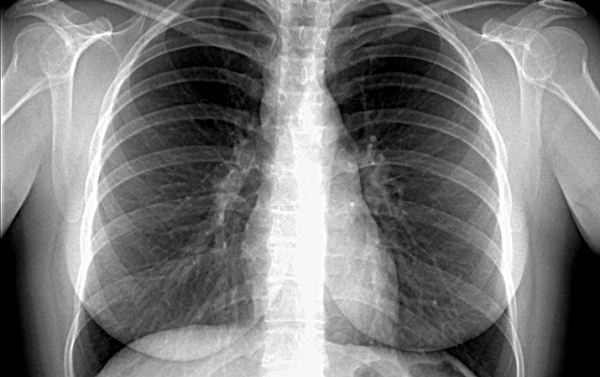

При саркоидозе внутригрудных лимфатических узлов (ВГЛУ) наблюдается расширение шпор трахеи и бронхов, сужение и деформация просветов бронхов, «саркоидозные эктазии» — расширенные, утолщенные, извитые сосуды в виде редкой сети или отдельных крупных сплетений. При саркоидозе ВГЛУ и легких такого рода изменения выражены меньше, но чаще встречаются собственно саркоидозные, связанные с гранулематозным поражением бронхиального дерева. При саркоидозе легких на первый план выходят воспалительные процессы в бронхиальном дереве. Поражение внутригрудных лимфатических узлов встречается более чем в 90 % случаев (см. рис. 2). Асимметричное увеличение ВГЛУ наблюдается в 10 % случаев.

Рис. 2. Рентгенограмма органов грудной клетки при саркоидозе 1-й ст. (патология выявлена при прохождении планового профилактического осмотра, бессимптомное течение).